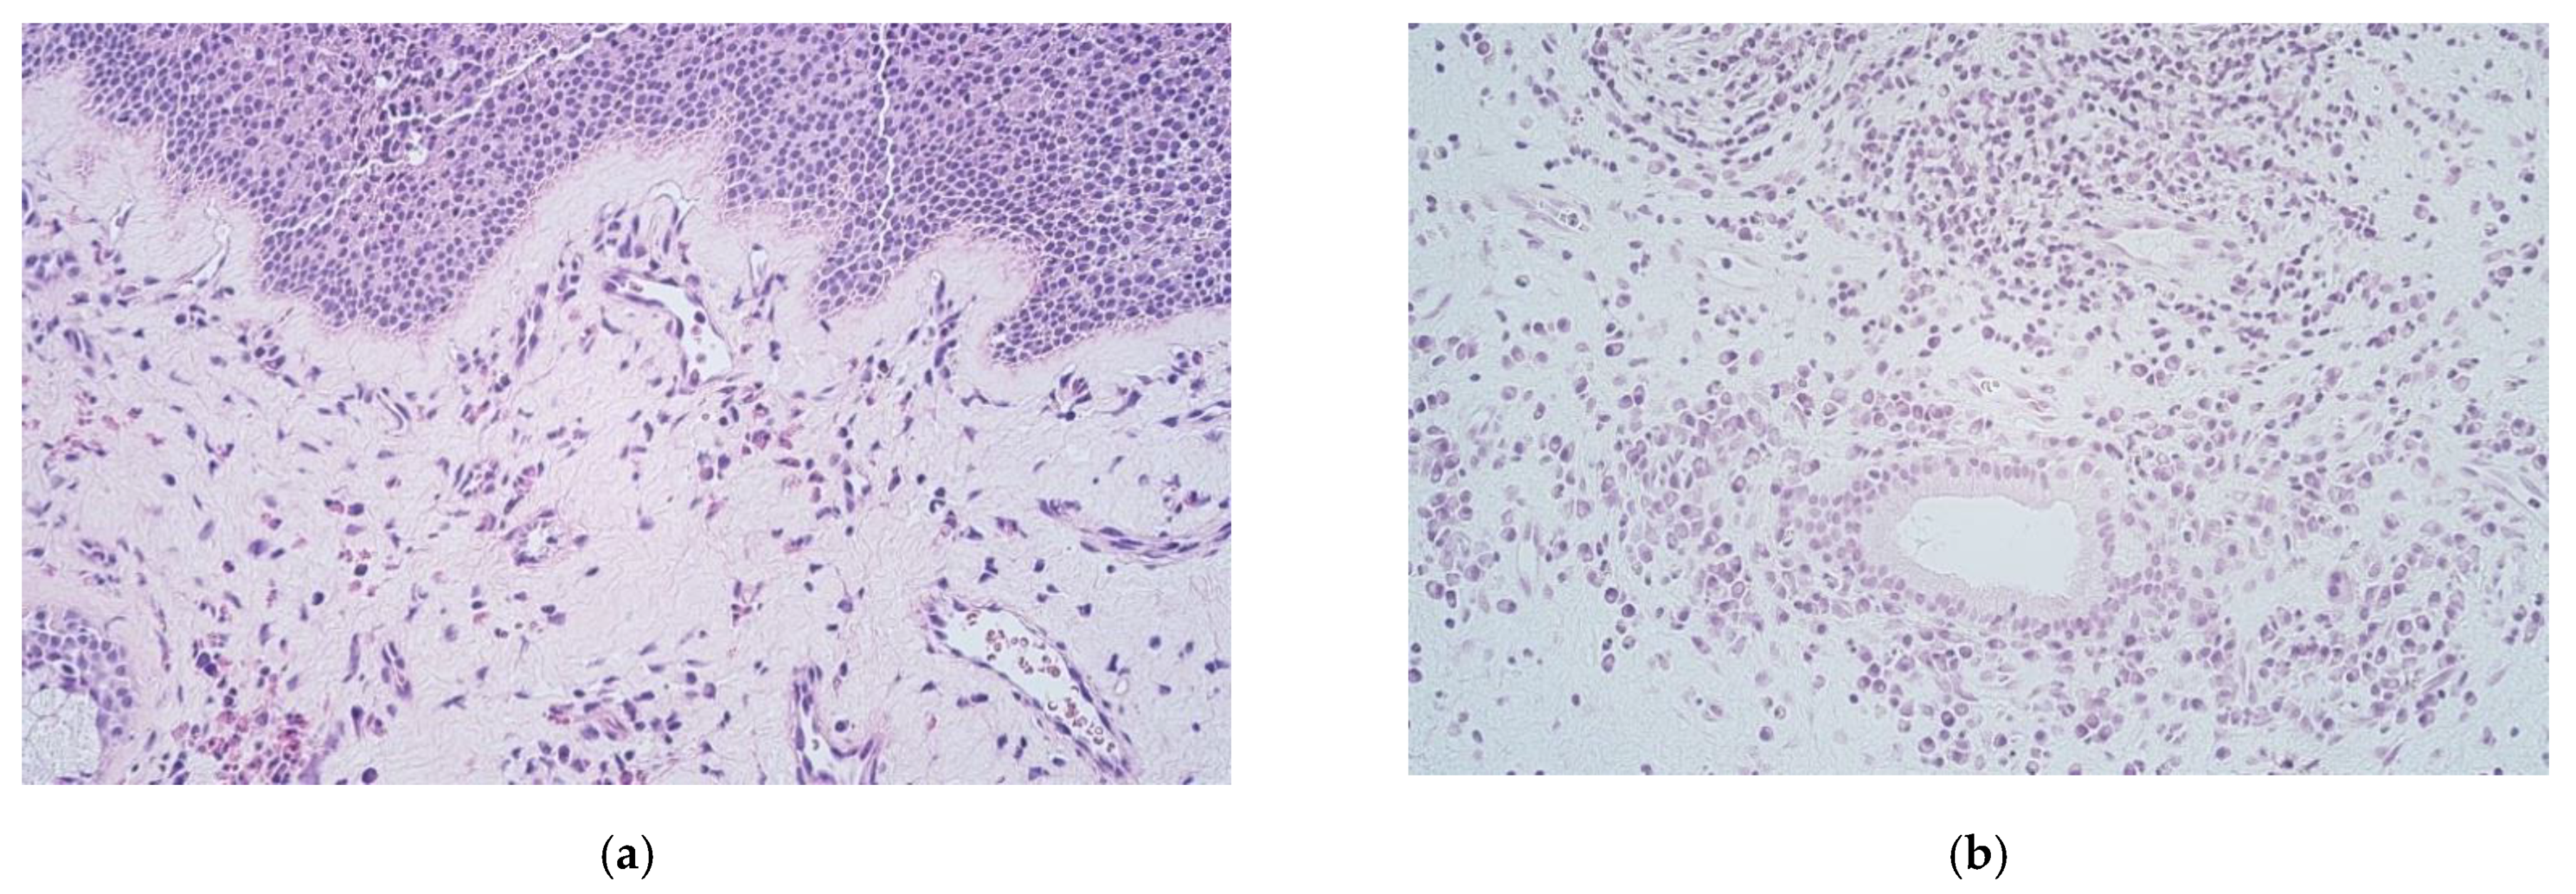

3. Results